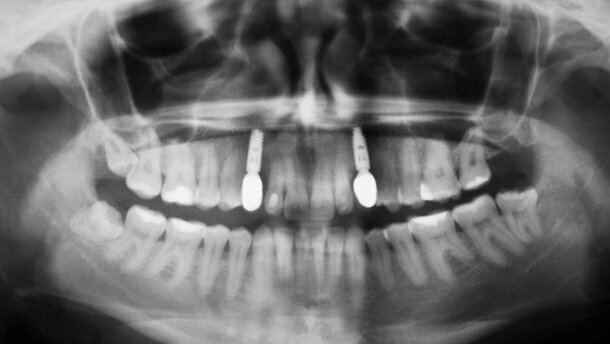

W przedstawionym przypadku zaprezentowano etapy leczenia i uzyskane rezultaty związane z pokryciem recesji tkanek miękkich w obrębie zębów przedtrzonowych po prawej stronie szczęki.

Przed wykonaniem końcowych rekonstrukcji protetycznych w postaci koron licowanych porcelaną opartych na implantach wszczepionych w pozycjach kłów, pacjentka oczekiwała poprawy stanu dziąseł w pozycjach zębów przedtrzonowych. Obnażeniu powierzchni korzeni towarzyszył silna nadwrażliwość. Dodatkowo, ze względu na wysoką dynamikę wargi górnej, defekty widoczne były w uśmiechu. Stan ten pogłębił się na przestrzeni ostatnich kilku lat. W badaniu widoczna była także bardzo wąska strefa dziąsła nieruchomego i cienki fenotyp. Po przeanalizowaniu stanu miejscowego zdecydowano o wykonaniu zabiegu pokrycia recesji korzeniowych oraz pogrubienia tkanek miękkich z wykorzystaniem matrycy kolagenowej mucoderm® firmy botiss®.

Pokrycie recesji było jednym z etapów leczenia kompleksowego. W pierwszym etapie wprowadzono implanty Ankylos® w pozycje brakujących zębów 3. i po upływie 5 miesięcy wykonano przykręcane korony tymczasowe. Korony te pozostawiono na 3 miesiące, aby uzyskać stabilizację tkanek miękkich wokół koron. Przed przystąpieniem do końcowej fazy protetycznej, zaplanowano zabieg pokrycia recesji w obrębie zębów przedtrzonowych. Wszystkie etapy leczenia zostały udokumentowane, a szczegóły uwidoczniono na zdjęciach.

Przedstawiony przypadek jest udokumentowanym doniesieniem klinicznym z wykorzystaniem matrycy kolagenowej mucoderm® do pokrycia recesji korzeniowych. Krytyczna analiza wymaga porównania obiektywnych parametrów periodontologicznych. Wielkość recesji reprezentowana przez odległość od połączenia szkliwno-cementowego do najwyższego zenitu wolnego brzegu dziąsłowego wynosiła 4 mm w pozycji zęba 14 przed rozpoczęciem leczenia. Po 8 miesiącach od przeprowadzenia leczenia ten sam parametr wyniósł 1,5 mm.

Badanie ruchomości dziąsła przed zabiegiem wykazało wąską strefę dziąsła nieruchomego wynoszącą ok. 2 mm. Test pociągania i pomiar tej strefy po 8 miesiącach od przeprowadzonego zabiegu wskazuje na poprawę szerokości strefy dziąsła nieruchomego do 4 mm. Parametr grubości błony śluzowej nie został zmierzony, co stwarza trudność w obiektywnej ocenie zmian grubości błony śluzowej na przestrzeni czasu. Optyczna analiza dokumentacji zdjęciowej pozwala jednak zauważyć zdecydowaną zmianę grubości błony śluzowej na przestrzeni pierwszych miesięcy po przeprowadzeniu zabiegu.